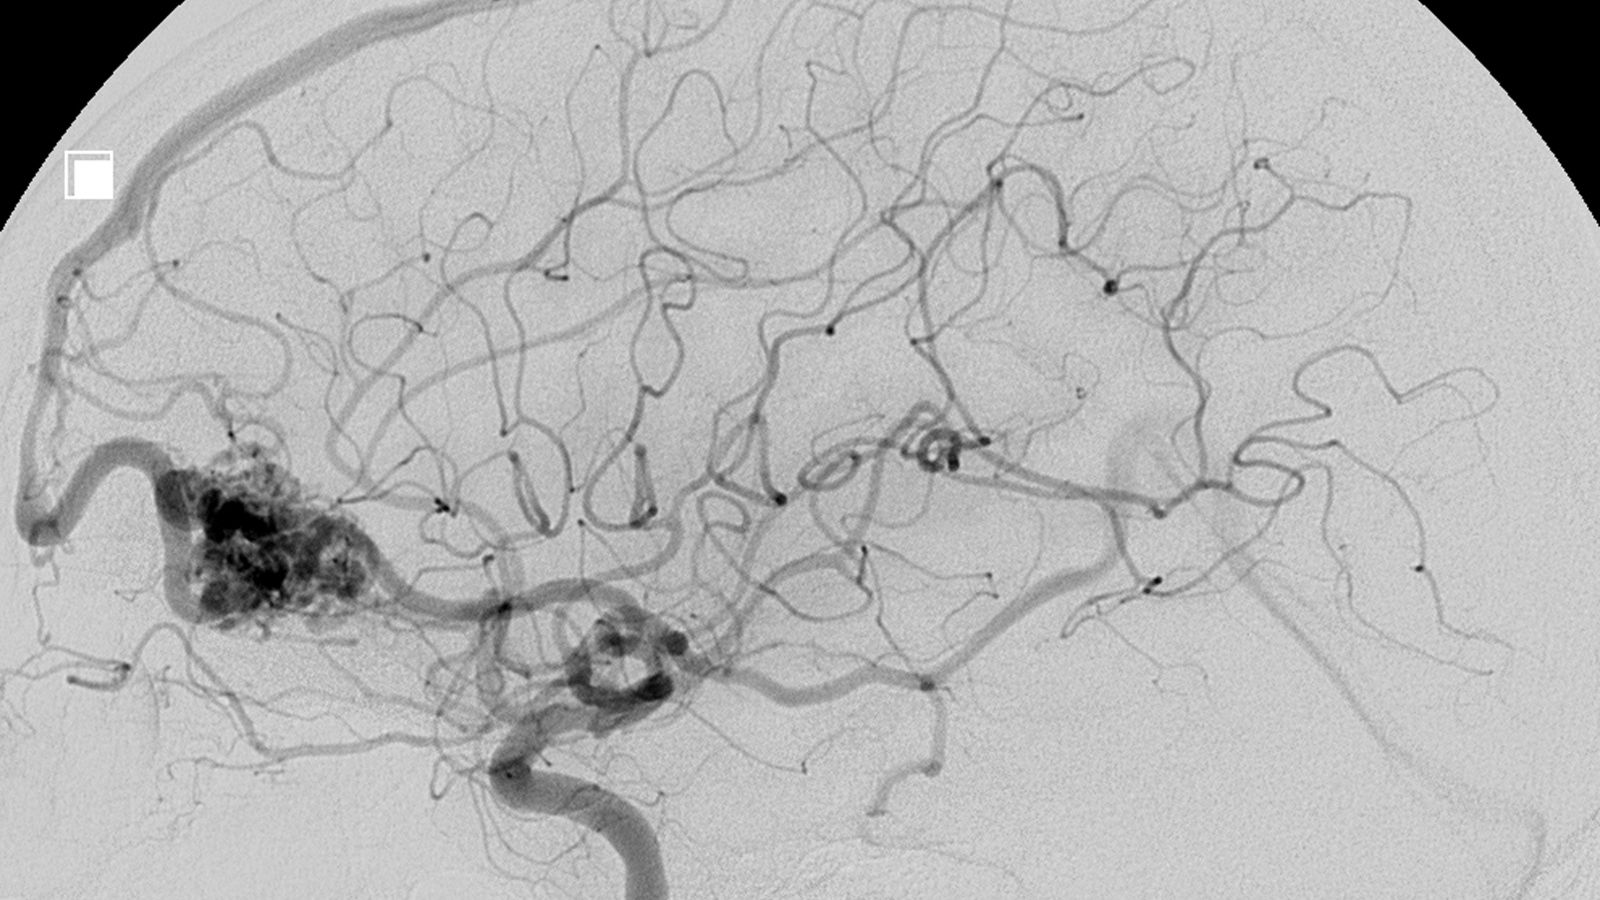

Biküspit aort teşhisi çoğu zaman beklenmedik bir anda, başka bir sebeple yapılan rutin bir doktor muayenesi sırasında konulur. Genellikle ilk ipucu, doktorun stetoskopla kalbi dinlerken duyduğu ve “üfürüm” adı verilen anormal bir sestir. Bu üfürüm, kanın normal olmayan, iki yaprakçıklı kapaktan geçerken çıkardığı çalkantılı akışın sesidir. Bazen üfürüme ek olarak sertleşmiş kapağın açılırken çıkardığı keskin bir “tıklama” sesi de duyulabilir.

Bu bulgular üzerine doktor, durumu netleştirmek için ek tetkikler ister. Biküspit aort tanısında altın standart yöntem ekokardiyografi (EKO), yani kalp ultrasonudur. Bu ağrısız ve zararsız test, ses dalgaları kullanarak kalbin ve kapakçıkların hareketli görüntülerini oluşturur. EKO sayesinde kapağın iki yaprakçıklı yapısı net bir şekilde görülür, kireçlenme olup olmadığı, ne kadar daraldığı veya ne kadar kaçırdığı ölçülebilir. Ayrıca kalbin bu durumdan ne kadar etkilendiği, kalp kasının kalınlaşıp kalınlaşmadığı ve pompalama gücü de değerlendirilir. Aort damarının çapını daha detaylı ölçmek için ise Bilgisayarlı Tomografi (BT) veya Kardiyak Manyetik Rezonans (MRG) gibi ileri görüntüleme yöntemlerine başvurulabilir.